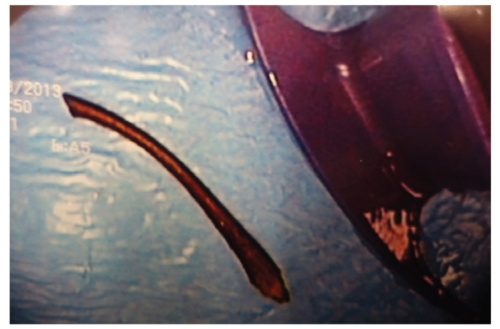

Figure 2. The foreign body after retrieval in the endoscopic suite. It appears to be a long chicken bone